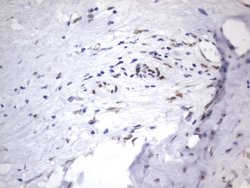

RBFOX1 Mouse anti-Human, Clone: OTI4F9, lyophilized, TrueMAB™

| Immunohistochemistry (Paraffin), Western Blot | |